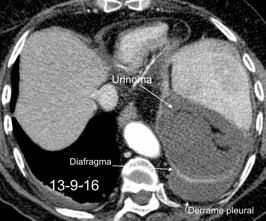

27. DERRAME PLEURAL IZQUIERDO. URINOMA

Urinoma

Enfermedad subdiafragmática Urinoma

Raro. Trasudado.